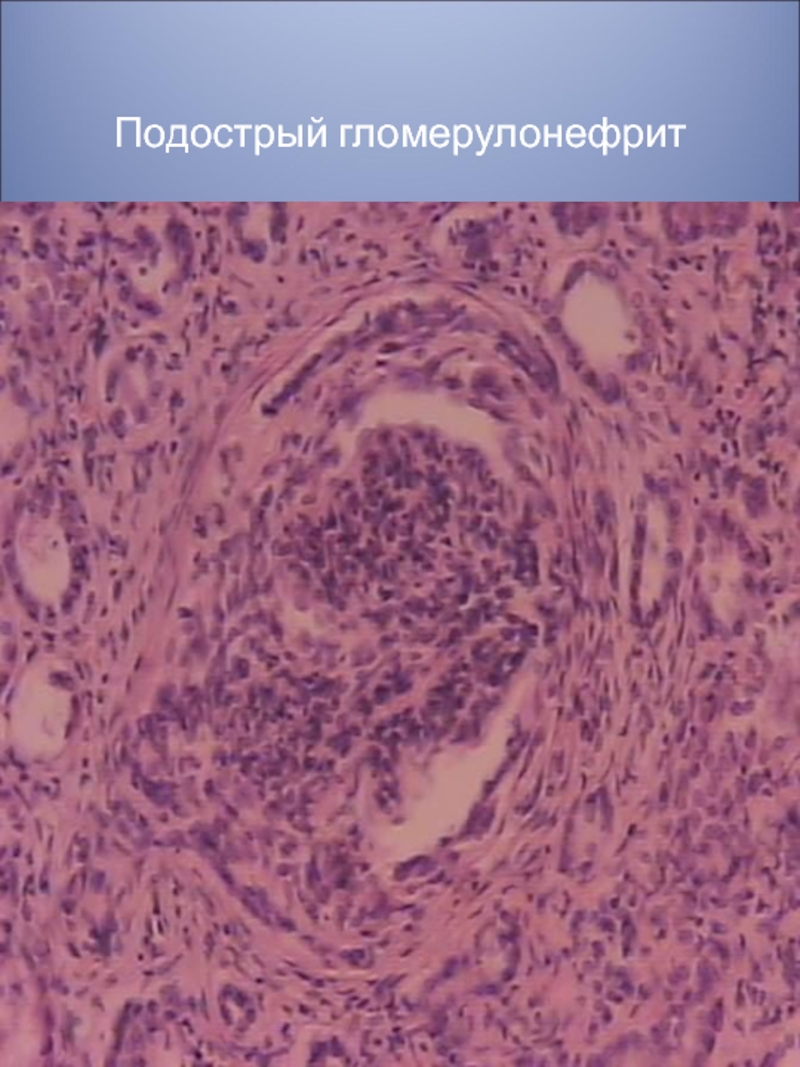

Механизм остро го диффузного гломерулонефрита